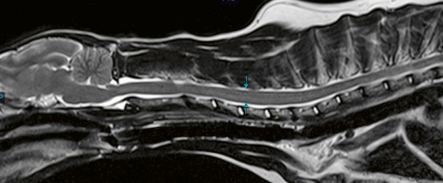

1.5T 60 cm Bore size

Applications for all body parts

Protocols included for Neuro, Musculoskeletal, Cardiac, Body and Oncology.